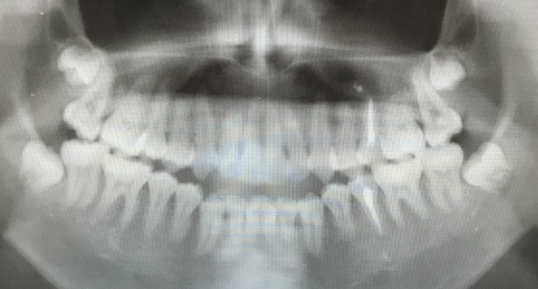

После снятия брекетов носил пластинку около 1 год 5 месяцев на ночь. К вечеру чувствовал, что пластинка садится туго, к утру все нормально. В 15 лет заметили, что прикус открытый. Сделали панорамный снимок. Определили, что 8-ки неправильно расположены в челюсти.

Через полтора года сделали еще один панорамный снимок, корни уже почти сформированы. Все стоматологи говорят, что нужно удалять 8-ки. Еще есть КТ. Сегодня были на консультации у стоматолога-хирурга. Он сказал, что очень сложно, но можно удалить пока один зуб снизу слева. Верхние предложил пока не трогать, подождать, когда они ближе подойдут.

Нужно ли удалять 8-ки (сейчас внизу)? Что делать с верхними 8-ми? Может ли удаление 8-ок немного расслабить зубной ряд, и хоть как то улучшить прикус?

В обязательном порядке требуется повторное эндодонтическое лечение. Восьмые зубы удалять надо, но, важно определить, не расположены ли верхние на границе с верхнечелюстной пазухой, а нижние в нижнечелюстном канале. Определить это можно по трехмерному снимку. Если зубы лежат в области этих анатомических образований, то необходимо подождать и провести удаление позже. Но требуется коррекция открытого прикуса.